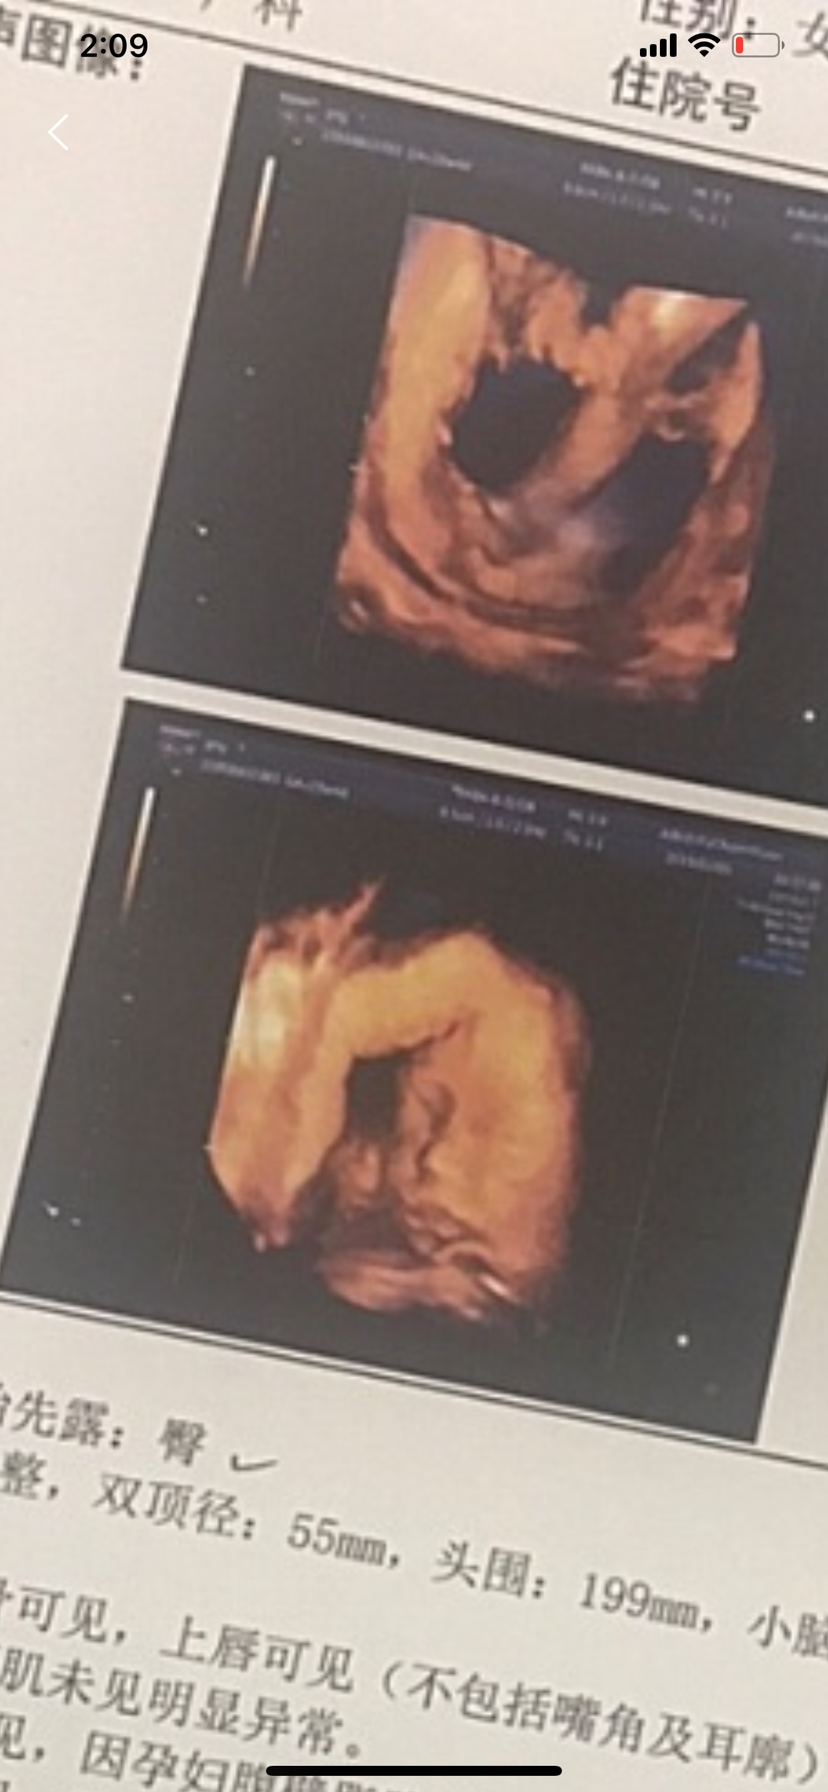

孕7周+3天

孕16周+1天